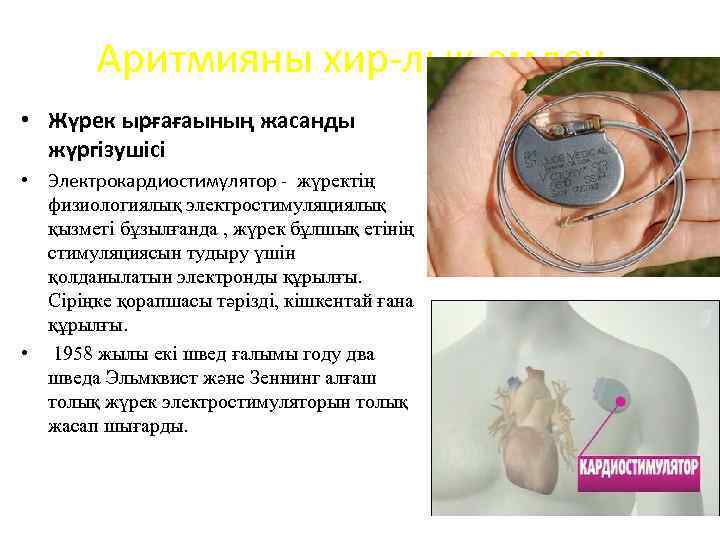

Аритмияны хир-лық емдеу • Жүрек ырғағаының жасанды жүргізушісі • Электрокардиостимулятор - жүректің физиологиялық электростимуляциялық қызметі бұзылғанда , жүрек бұлшық етінің стимуляциясын тудыру үшін қолданылатын электронды құрылғы. Сіріңке қорапшасы тәрізді, кішкентай ғана құрылғы. • 1958 жылы екі швед ғалымы году два шведа Эльмквист және Зеннинг алғаш толық жүрек электростимуляторын толық жасап шығарды.

Аритмияны хир-лық емдеу • Жүрек ырғағаының жасанды жүргізушісі • Электрокардиостимулятор - жүректің физиологиялық электростимуляциялық қызметі бұзылғанда , жүрек бұлшық етінің стимуляциясын тудыру үшін қолданылатын электронды құрылғы. Сіріңке қорапшасы тәрізді, кішкентай ғана құрылғы. • 1958 жылы екі швед ғалымы году два шведа Эльмквист және Зеннинг алғаш толық жүрек электростимуляторын толық жасап шығарды.